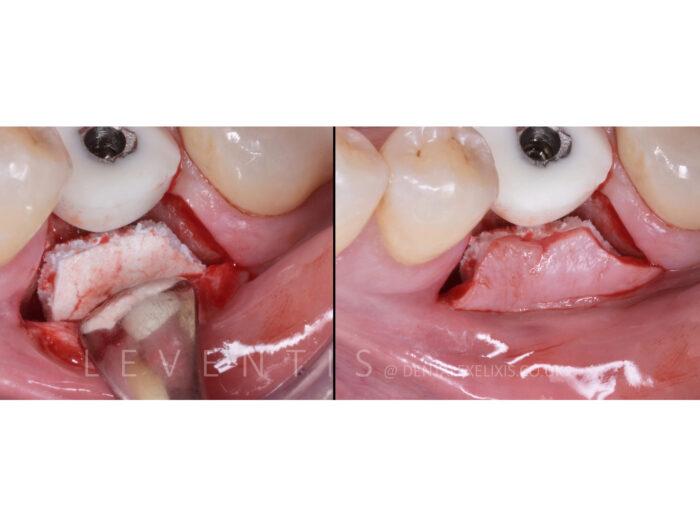

W pełni wchłanialna, tworząca przestrzeń matryca podtrzymująca tkankę, połączona z przeszczepem kostnym.

Działa jako szkielet, który umożliwia tworzenie nowej kości. Do stabilizacji możemy użyć pinów lub śrub do osteosyntezy.

- Początkowo następuje resorpcja krzemianów, indukując angiogenezę, zapewniając jednocześnie rusztowanie osteoprzewodzące wspierające tworzenie nowej kości.

- Zewnętrzna struktura polimerowej gąbki sprzyja adhezji komórek mezenchymalnych, wzmacniając wiązanie fibrynowe i promując dodatkowo rozwój nowej tkanki łącznej.

- Pełna resorpcja po ok. 5 miesiącach.